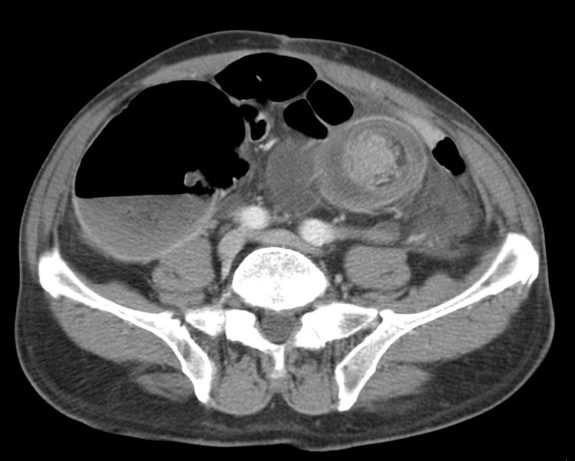

- El hallazgo patognomónico es el signo de la escarapela o diana identificable en la TC o ecografía.

- Podemos ver la imagen de «Intestino dentro de intestino” gracias a las reconstrucciones multiplanares.

Aunque el diagnóstico es sencillo, la TC es insuficiente para determinar la causa subyacente. Existen una serie de hallazgos que nos permiten caracterizar la invaginacion y valorar la gravedad, lo cual determina el tratamiento a seguir.